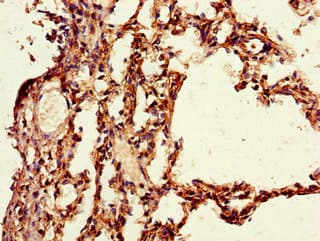

Anti-PAIP2 antibody(ab237803)

Rabbit Polyclonal PAIP2 antibody. Suitable for WB, IHC-P, ICC/IF and reacts with Human, Mouse samples. Immunogen corresponding to Recombinant Full Length Protein corresponding to Human PAIP2.